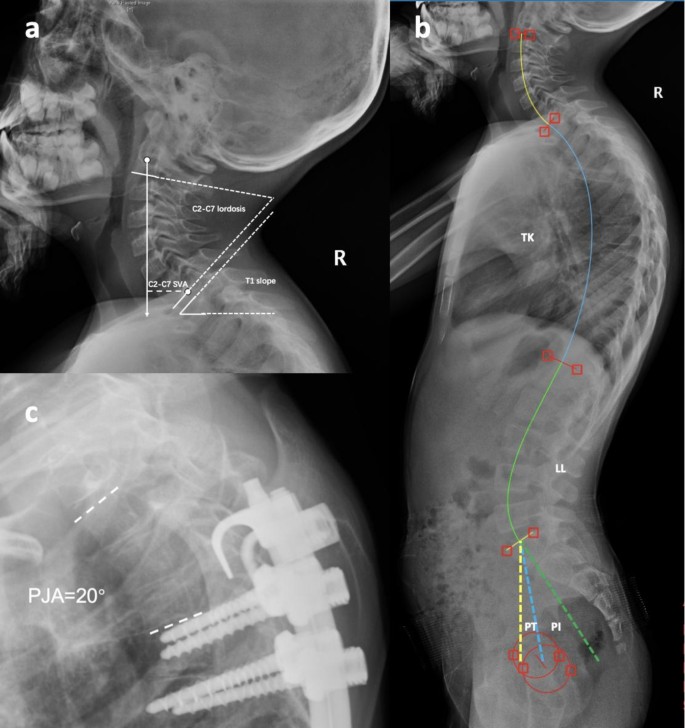

Radiographs (Fig. 1). PACS (Picture Archiving & Communication System) was used for radiographic measurements. A-P radiographic measurements included the main thoracic scoliosis Cobb angle, the distance between cervical seven plumb lines (C7PL), and the centre sacral vertical line. Lateral radiographic measures included C2-C7 cervical lordosis (CL), T1 slope, C2-C7 sagittal vertical axis (C2-7 SVA), T2-T12 thoracic kyphosis (TK), C7-S1 sagittal vertical axis (C7-S1 SVA), proximal junctional angle (PJA), lumbar lordosis, sacral slope, pelvic tilt (PT) and pelvic incidence (PI).

The measurement demonstration of C2-C7 lordosis, T1 slope and C2-C7 sagittal vertical axis distance (a), thoracic kyphosis (TK), lumbar lordosis (LL), pelvic incidence (PI, angle between the green and blue dotted lines) and pelvic tilt (PT, angle between the yellow and blue dotted lines) (b). Proximal junctional angle (PJA) is defined as the sagittal Cobb angle between the upper instrumented vertebrae (UIV) and the 2nd vertebrae above the UIV (c).